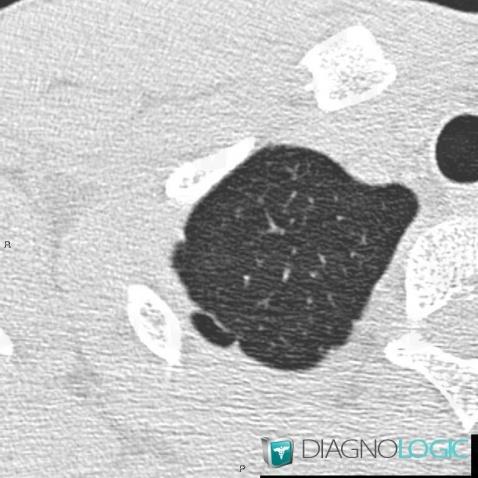

Pneumothorax, Plèvre, Radio

Voici les informations spécifiques à l'image clé ci dessus:

- Diagnostic Pneumothorax, Localisation(s) Plèvre, comportant les gammes